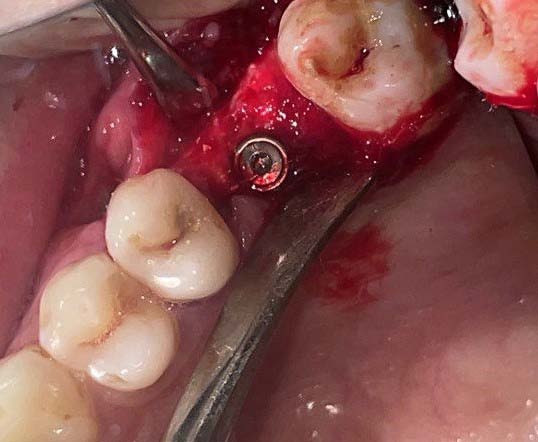

After the surgical preparation mentioned above, a one-stage implant placement technique was carried out. The flap was extended up to the inferior border of the zygoma, to allow the visibility of the lateral wall of the maxillary sinus. The lateral window was created using the dome drill of 5.0 mm diameter with a stopper system (0.5mm increments) for effective depth control. When the maximum desired depth was achieved with the 0.5 mm drill stopper, it was changed to a 1.0 mm stopper, and drilling was proceeded chronologically while scrutinizing for any perforation. The drilling of the osseous wall continued with increasing depths and stoppers till full penetration of the lateral wall was achieved and the bony window was removed in-toto (Figure 2). Sinus curettes were then used to gently lift the sinus membrane by moving it between the membrane and bony wall anteriorly, posteriorly, and medially. Once the membrane was free of all the attachments, we encountered the movement of the membrane that was concomitant with the breathing.

The osteotomy was then prepared into the ridge and an implant of the desired length was placed and the cover screw was tightened (Figure 3). After that, the apical portion of the implant was packed with a xenograft (Cerabone, Biotiss, Germany). The bony window, that was cut out, was placed back in the position and was covered with a PRFmembrane. Primary closure of the soft tissue was obtained. The flap was repositioned with a non-absorbable braided suture, first with horizontal mattress sutures, and, then with interrupted sutures to seal the crest (Figure 4). Postoperative instructions were provided to the patient (Table 1).